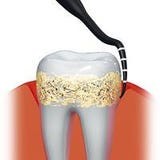

- subgingivale "unterirdische" Taschenreinigung

- Taschenmessung und Reinigung

- Kapillareffekt für Desinfektion

In Zahnfleischtaschen können sich äußerst aggressive Bakterien verbergen. Ist eine Zahnfleischtasche tiefer als 3 - 3,5 mm, ist eine Behandlung durch Ihren Zahnarzt dringend erforderlich. Mit dem Pocket Scouter können Sie die Tiefe der Zahnfleischtaschen selber messen: Ist die Tasche tiefer als der erste weiße Strich, begeben Sie sich bitte in Behandlung.

In Zahnfleischtaschen können sich äußerst aggressive Bakterien verbergen. Ist eine Zahnfleischtasche tiefer als 3 - 3,5 mm, ist eine Behandlung durch Ihren Zahnarzt dringend erforderlich. Mit dem Pocket Scouter können Sie die Tiefe der Zahnfleischtaschen selber messen: Ist die Tasche tiefer als der erste weiße Strich, begeben Sie sich bitte in Behandlung.